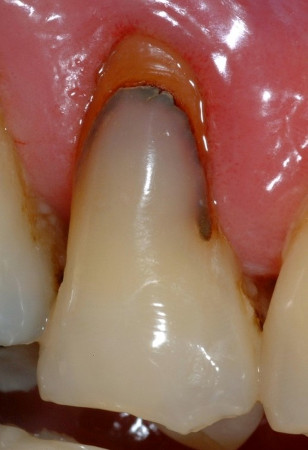

En ce qui concerne les verres hybrides, les seules données disponibles sont des études randomisées qui ont comparé ce matériau avec les résines composites dans les lésions non carieuses (Fig. 4).

Fig. 4a : Dans les études cliniques randomisées et contrôlées, les verres hybrides montrent des résultats prometteurs pour la restauration des lésions cervicales. a) Lésion cervicale non carieuse, avant traitement,

Fig. 4b : Restauration initiale par un verre hybride.

Fig. 4ac: Même restauration après 6,5 ans (Avec l’aimable autorisation du Pr M. Basso, Italie).

L’étude la plus intéressante concernant les caries radiculaires est celle qui a évalué un verre hybride (EQUIA Forte, GC) par rapport à des restaurations en résine composite (Filtek Supreme XTE, 3M) pour le traitement de lésions radiculaires non carieuses présentant une dentine sclérotique chez 88 patients d’âge moyen et plus avancé (50 à 70 ans).10

Une évaluation de la survie, de la qualité et des coûts de 92 restaurations, mises en place sans aucune préparation mécanique (ayant finalement entraîné des taux d’échec annuels élevés pour les deux groupes) a été réalisée sur une durée de 36 mois. La qualité des restaurations a été évaluée après 1, 18 et 36 mois selon les critères de la Fédération dentaire internationale (FDI). Les coûts ont été évalués à l’aide d’une approche reposant sur le microcosting (comptabilisation du temps utilisé pour la mise en place du matériau) et, pendant le suivi, sur les prestations de l’assurance maladie obligatoire en Allemagne. Après 36 mois, une perte totale de rétention a été constatée pour 17 verres hybrides et 19 résines composites, et une perte partielle pour 5 verres hybrides. Les coûts liés aux verres hybrides étaient nettement inférieurs, tant au début de l’étude (verres hybrides : 32,57 euros [écart type 16,36 euros] par rapport aux résines composites : 44,25 euros [écart type 21,40 euros]) et sur toute la période de suivi (verres hybrides : 41,72 euros [écart type 25,08 euros] par rapport aux résines composites : 51,60 euros [écart type 26,17 euros]).